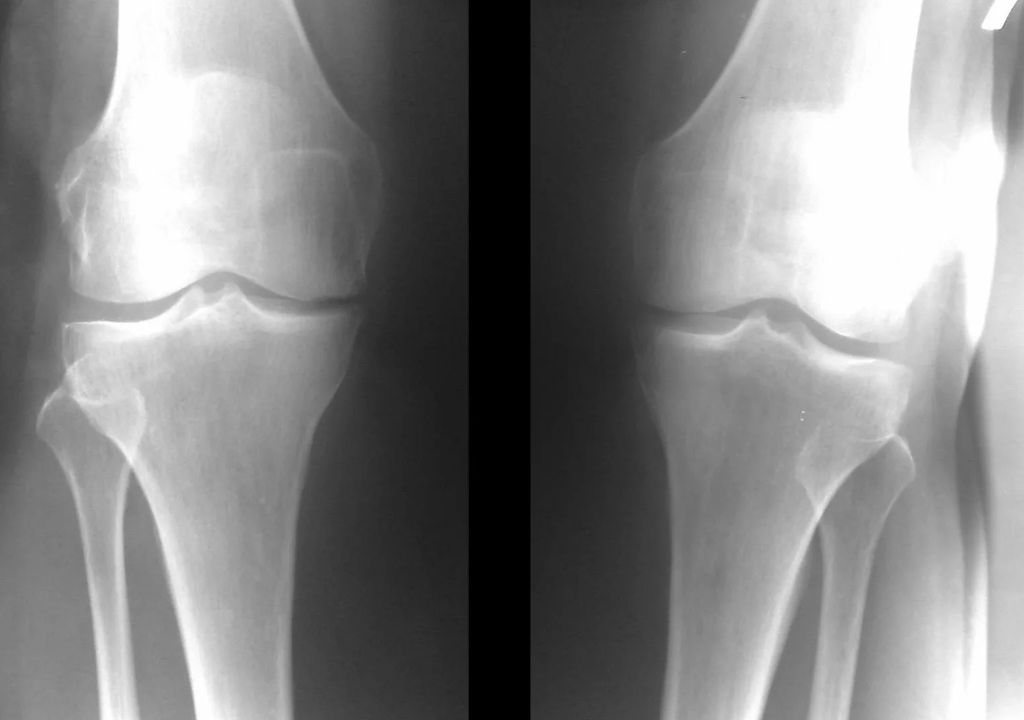

In the vast majority of cases, an examination and x-ray of the knee joint in two views (direct and lateral) are sufficient.Clinical data and imaging help determine the stage of the disease.

In the early stages of the disease, with minor changes in bone tissue, X-ray examination is not as valuable.At this stage, gonarthrosis can be diagnosed through arthroscopy.The precision of the method is very high;only its invasive nature and price can stop it.

Ultrasound does not allow clear visualization of changes in articular cartilage and intra-articular structures.With MRI, changes in the bone, cartilage and soft tissue structures of the joint, as well as in the subchondral bone, can be detected with an accuracy of 85%.Scintigraphy can be used to evaluate the metabolic activity of periarticular bone tissue.

Lack of cartilage in most affected areas, severe sclerosis (hardening) of the bone, many osteophytes, and acute narrowing or absence of the joint space.The pain is almost constant, walking is altered.Mobility is very limited and deformation of the joints is noticeable.NSAIDs, physical therapy and other standard methods of treating knee osteoarthritis are ineffective.